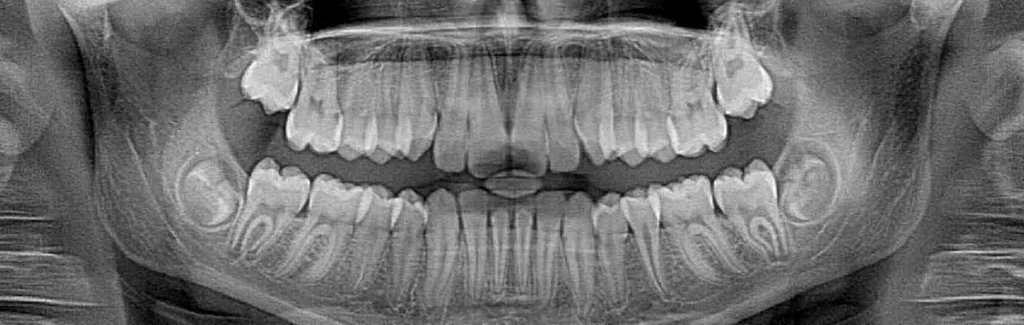

Dental X-rays enable dentists to see decay inside teeth that would not be visible to the naked eye. This allows us to act earlier against cavities, which is much better for the teeth. However, X-rays do expose patients to radiation, which is why you always wear a lead apron when the images are being taken. Thanks to advances in technology, there is now a safer way to take these images.

Film X-rays have been used in dentistry for decades. In the past few years, many forward-thinking dentists like Dr. Kerman have invested in digital X-ray technology. Film X-rays cost a bit less than digital X-rays but the increased exposure to film X-rays is more harmful to a patient’s overall health. Our digital X-ray emits as much as 85 percent less radiation than traditional X-ray technology.

Digital X-rays are one of the most important new advances in our office. We are not only able to reduce your exposure to radiation but also increase the diagnostic proficiency. In addition to increased diagnostics, we reduce the amount of harmful chemicals and other waste materials associated with traditional X-ray technology. The reduction in waste was a big consideration when deciding to invest in digital technology. We pride ourselves in being environmentally responsible.